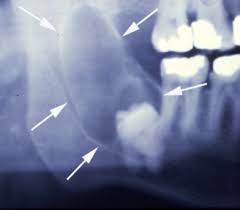

ฟันคุดคือ ฟันที่ไม่สามารถขึ้นได้เต็มที่ตามปกติ โดยมากมักจะเป็นในฟันกรามซี่สุดท้าย ( ในรูปคือ ฟันสีส้ม) สามารถเป็นได้ทั้งฟันบน และ ล่าง แต่ส่วนมากฟันล่างจะพบว่าเป็นฟันคุดได้มากกว่า ส่วนฟันซี่อื่น ๆ ถ้าขึ้นมาได้ไม่เต็มซี่ก็อาจเรียกว่าฟันคุดได้เหมือนกันค่ะ แต่ไม่ค่อยพบค่ะ

ทีนี้ฟันคุดมากคุดน้อยขึ้นอยู่กับตำแหน่งของฟัน ว่าฝังลึกลงไปในกระดูกมากน้อยแค่ไหนและมีความเอียงมากแค่ไหน (ลองดูรูปประกอบนะคะ) ถ้ายิ่งฝังลึกลงไปมาก หรือมีความเอียงมากก็จะยิ่งทำยากค่ะ ขั้นตอนการทำก็จะมีดังนี้ค่ะ 1. คุณหมอจะตรวจฟัน ซักประวัติว่ามีโรคประจำตัวไหม และ คุยกับคนไข้ก่อนว่าวันนี้จะผ่าฟันซี่นี้นะ เมื่อโอเคแล้วก็จะพาไป x-ray ดูฟันคุด 2. เมื่อได้ฟิล์มแล้ว หมออาจะบอกราคาค่าผ่าคร่าว ๆ ให้คนไข้ทราบว่าประมาณเท่าไหร่ 3. จากนั้นก็จะ เอายาชาแบบทา ทาไปที่เหงือกก่อนเพื่อลดความเจ็บปวดตอนฉีดยา แล้วค่อยฉีดยาชาอีกที 4. ระหว่างรอชา อาจจะให้ทานยาแก้อักเสบ และแก้ปวดกันไว้ก่อน(แล้วแต่เคสค่ะ) 5. เมื่อทดสอบดูพบว่าชาดีแล้วค่อยทำการผ่าฟันคุดค่ะ 6. ผ่าเสร็จก็รับยา อ่านข้อปฏิบัิตัวหลังผ่าฟันคุดแล้วกลับบ้านไ้ด้เลยค่ะ อีก 7 วันหมอจะมาดูแผล และตัดไหมที่เย็บไว้ค่ะ